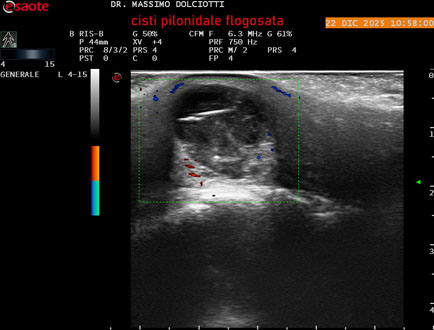

Strumento: Esaote MyLab Eight

Sonda: Lineare Multifrequenza 4-15 MHz

Età Paziente: M 29 anni

Motivazione dell'esame: da 3.giorni dolore, tumefazione ed arrossamento in regione coccigea

Commento all'esame: le immagini ed il video documentano formazione anecogena in sede coccige, delle dimensioni di 24,6 x 18,8 mm, da ricondurre a cisti pilonidale flogosata.

Conclusioni: cisti pilonidale flogosata (inflamed pilonidal cyst).

Presentazione: Dr. Massimo Dolciotti - Ancona